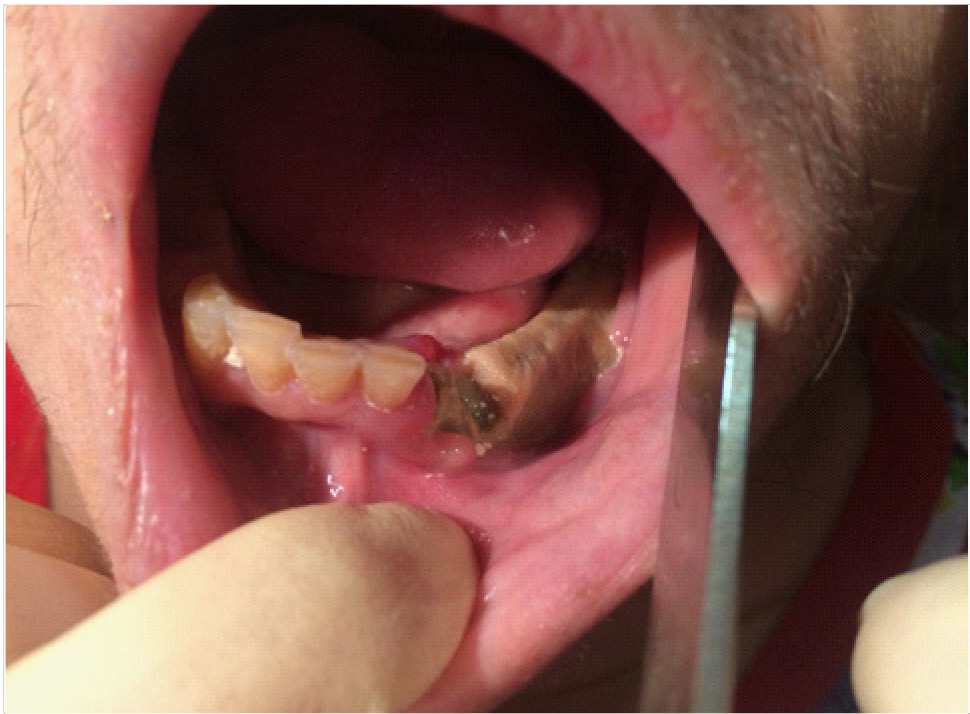

В полости рта: лунки 4.7, 4.5 зубов выполнены рыхлыми грануляциями с субтотальным остеонекрозом альвеолярной части нижней челюсти справа (рис. 2).

Рис. 2. Клинические проявления бисфосфонатного остеонекроза нижней челюсти справа у пациентки Б. в 2022 г.

Пальпация безболезненная. На ортопантомограмме определяются лунки зубов 4.7, 4.5 без явных признаков секвестрирования (рис. 3).

Рис. 3. Ортопантомограмма на этапе лечения остеонекроза нижней челюсти справа у пациентки Б. в 2022 г.